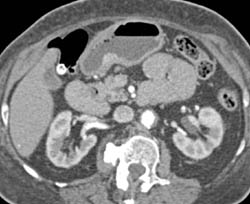

Subtle Tumor in Gastric Fundus Was Biopsy Proven Adenocarcinoma